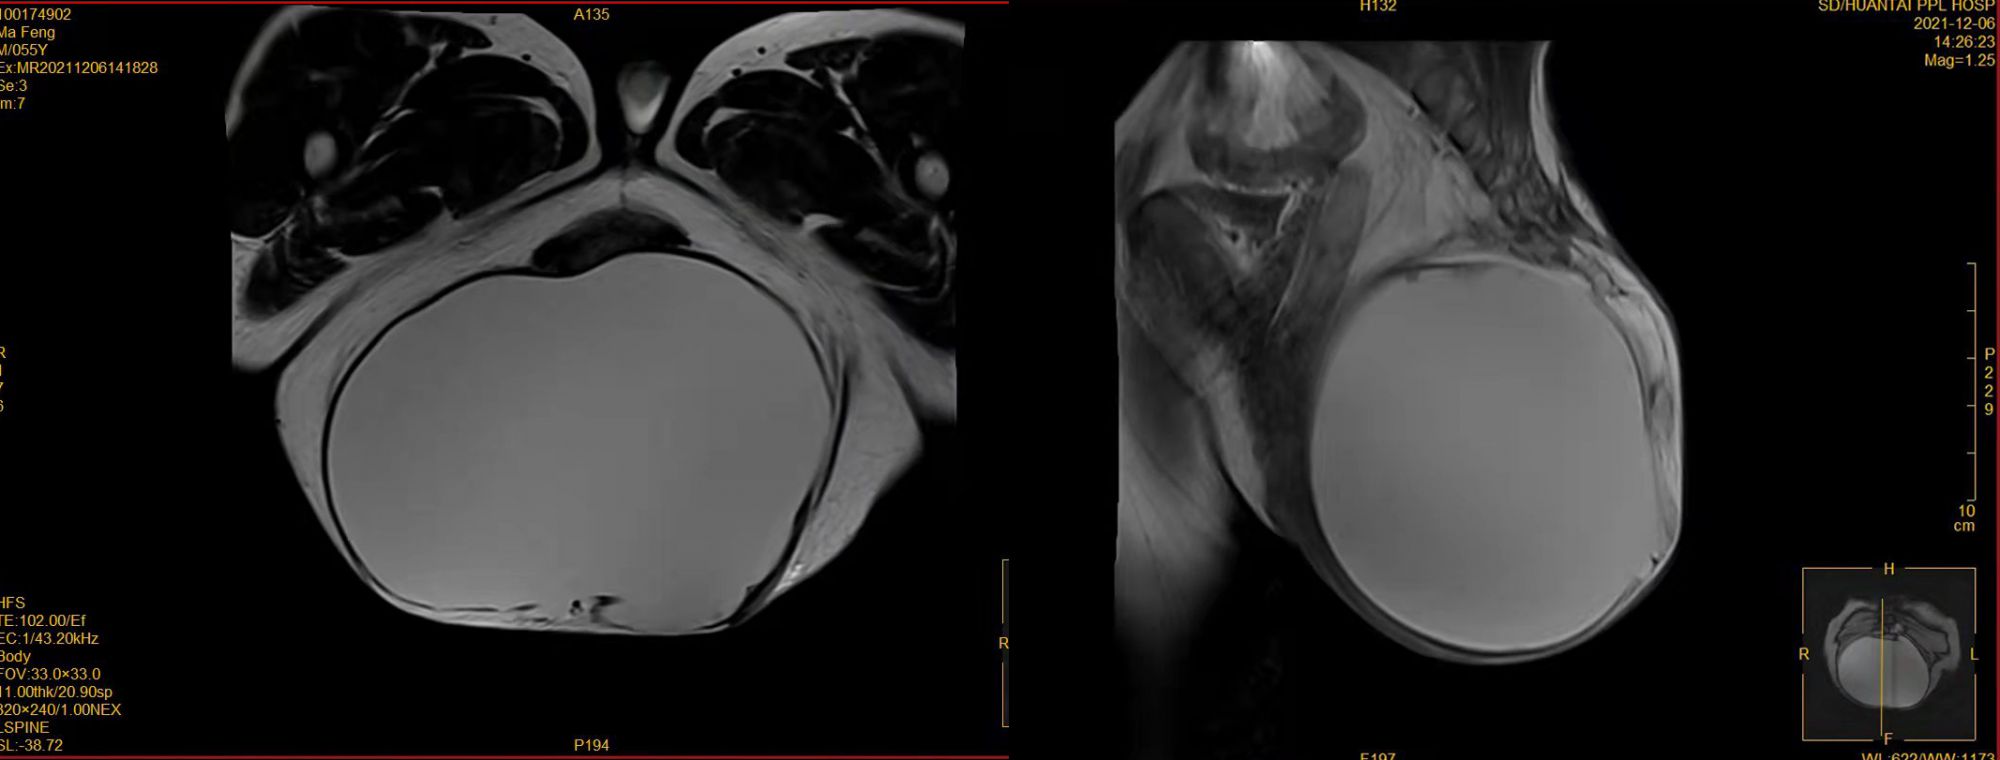

55岁的马先生,臀部生长一巨大肿物,大小约40cm×30cm(比篮球还大),行动十分不便,晚上睡觉只能蹲在床边,万般无奈之下来到我院肛肠外科咨询。 据了解该患者病史长达50余年之久,期间多次到省市级医院寻求治疗无果,来到我院后经过详细查体及全面辅助检查,考虑患者可能患了一种世界上极为罕见的疾病:尾肠囊肿,需手术治疗。但手术复杂,难度极高,切除过程易损伤直肠、输尿管、骶前静脉及盆部大血管,严重时可造成失血性休克,甚至危及生命。同时该患者患有肝硬化、血小板减少性紫癜多年,长期服药,凝血功能差,3年前行脾动脉栓塞术后曾出现过病危,经积极抢救才病情好转。 以上多种因素均给患者的手术带来了极大的难度和风险,肛肠外科通过反复多次病例讨论,查阅大量专业资料,并邀请血液风湿科、肝胆外科、神经外科、骨科、影像科、输血科及麻醉科等多个科室进行会诊分析,针对出血风险制定了最佳诊疗及手术方案。 2021年12月15日,肛肠外科在麻醉科及手术室团队配合下成功将肿物完全分离,并修补各层肌肉组织,恢复盆底及臀部生理状态。术中出血约2500ml,术后清点标本,肿物内包裹的暗红色液体约4000ml。术后病理证实患者为尾肠囊肿。现患者术后恢复良好,行动方便,刀口拆线出院。 尾肠囊肿绝大多数发生于骶前-直肠后间隙,是一种十分罕见的先天性病变,至今世界各国文献报告该疾病不到百例,通常大小在1-22cm之间。该患者囊肿之巨大,属世界罕见。尾肠囊肿患者以女性居多,均为先天性,在胚胎发育期间形成,尾肠囊肿易感染、易恶变,发现后应及时系统治疗,避免延误病情。 肛肠外科已成功开展多例骶尾部肿瘤切除手术,但如此巨大且与血管关系复杂的肿瘤尚属首次。手术的成功是医院多学科协作诊疗模式(MDT)和综合诊疗水平的体现,保障了医疗安全,改善了医疗服务,得到了患者的高度评价。 同时我院肛肠外科还可开展腹腔镜下结直肠肿瘤的微创手术、NOSES手术(经自然腔道取标本手术)、ELAPE手术(经肛提肌外腹会阴联合直肠癌根治术)、直肠癌肝转移的联合手术等,均取得了良好的效果。 咨询电话: 0533-8228197 金 鹤 18505338391 宋晓慧 18505338398 肖海洋 18505338393 巩发才 18505338395 成向廷 18505338392 巩 纬 18906433193 病房:病房楼6楼东区 门诊:门诊楼二楼东北角(超声科对面)外科诊区